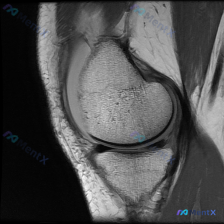

看到一个有意思的影像讨论病例,整理一下资料和思路分享给大家。 病例背景 提问:单张膝关节冠状位MRI图像,问题是图像中可见的异常是什么,提示半月板异常。 影像初步分析 先确认这张影像的基本信息:这是膝关节冠状位MRI,对比良好,骨髓信号正常,可以看到股骨远端、胫骨近端、内外侧关节间隙、半月板和侧副韧...

看到一个很典型的临床-影像矛盾病例,整理出来和大家分享思路。 病例核心信息 这是一张膝关节矢状位MRI单张图像,临床关注点为「半月板异常」,我们先来看影像的全面评估结果: 1. 骨骼结构:股骨远端、胫骨近端、髌骨轮廓完整,无明显骨皮质中断或骨折 2. 关节软骨:股骨、胫骨关节面软骨信号均匀,无明显剥...